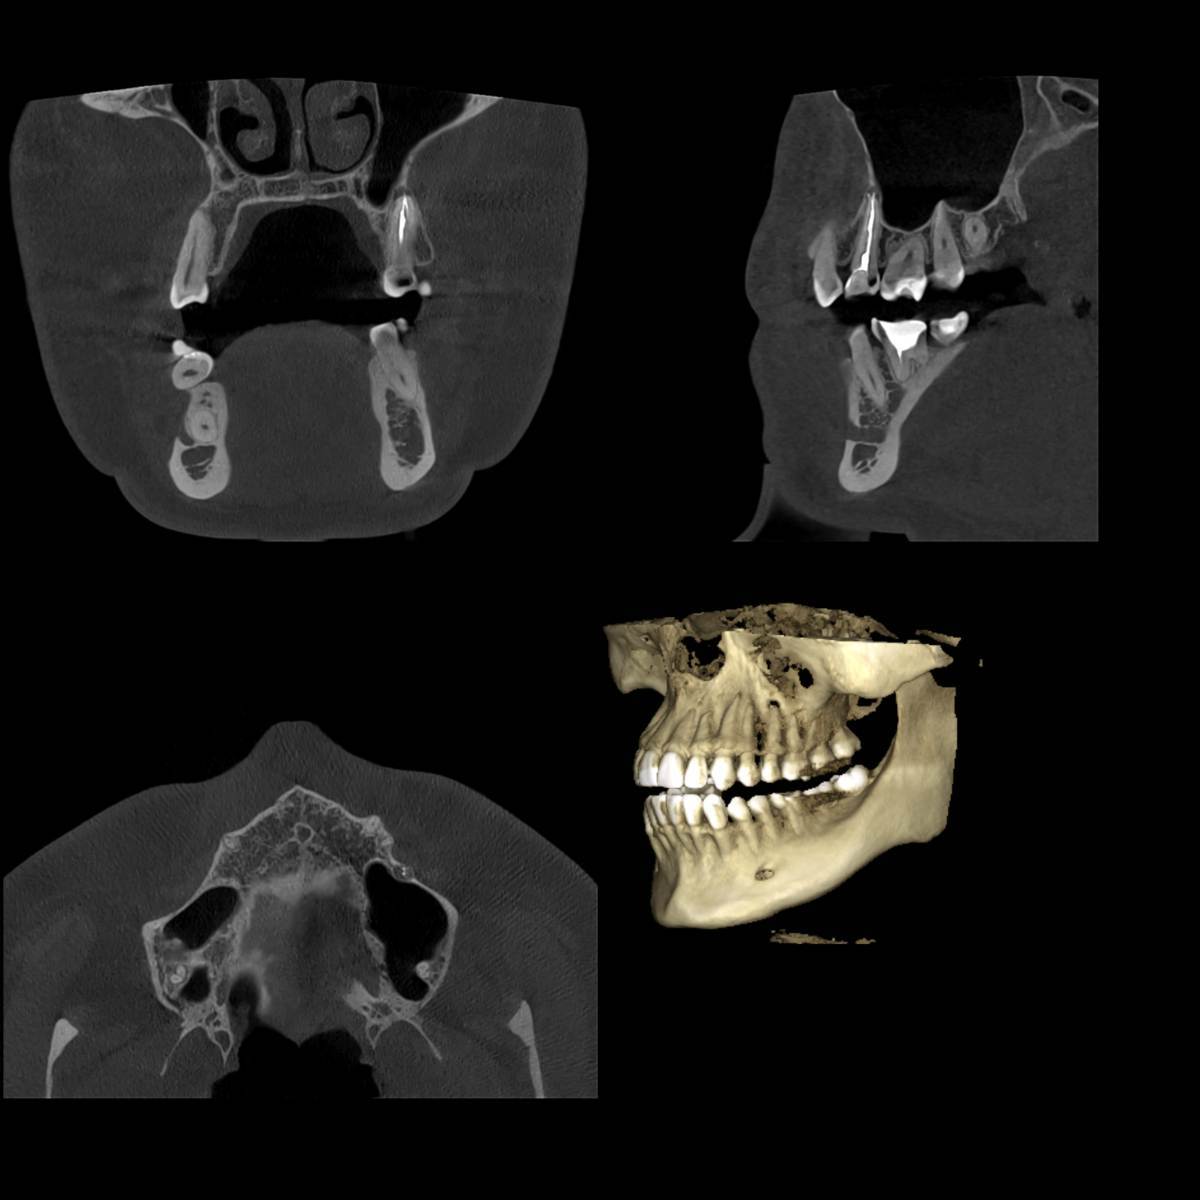

Л93 Опубликовано Понедельник в 19:05 Автор Поделиться Опубликовано Понедельник в 19:05 Этот снимок был сделан 6 лет назад перед началом лечения. Ссылка на комментарий

Женька Опубликовано Понедельник в 19:36 Поделиться Опубликовано Понедельник в 19:36 Здравствуйте! Криминала не вижу по Вашему 25 зубу. Но это лишь один срез, не дающий полной картины. По 8... интересно посмотреть в полости рта. Потому что на снимке 6 лет назад она действительно не прорезалась, а вот на свежем вполне себе должна жевать с нижней 8. Ссылка на комментарий